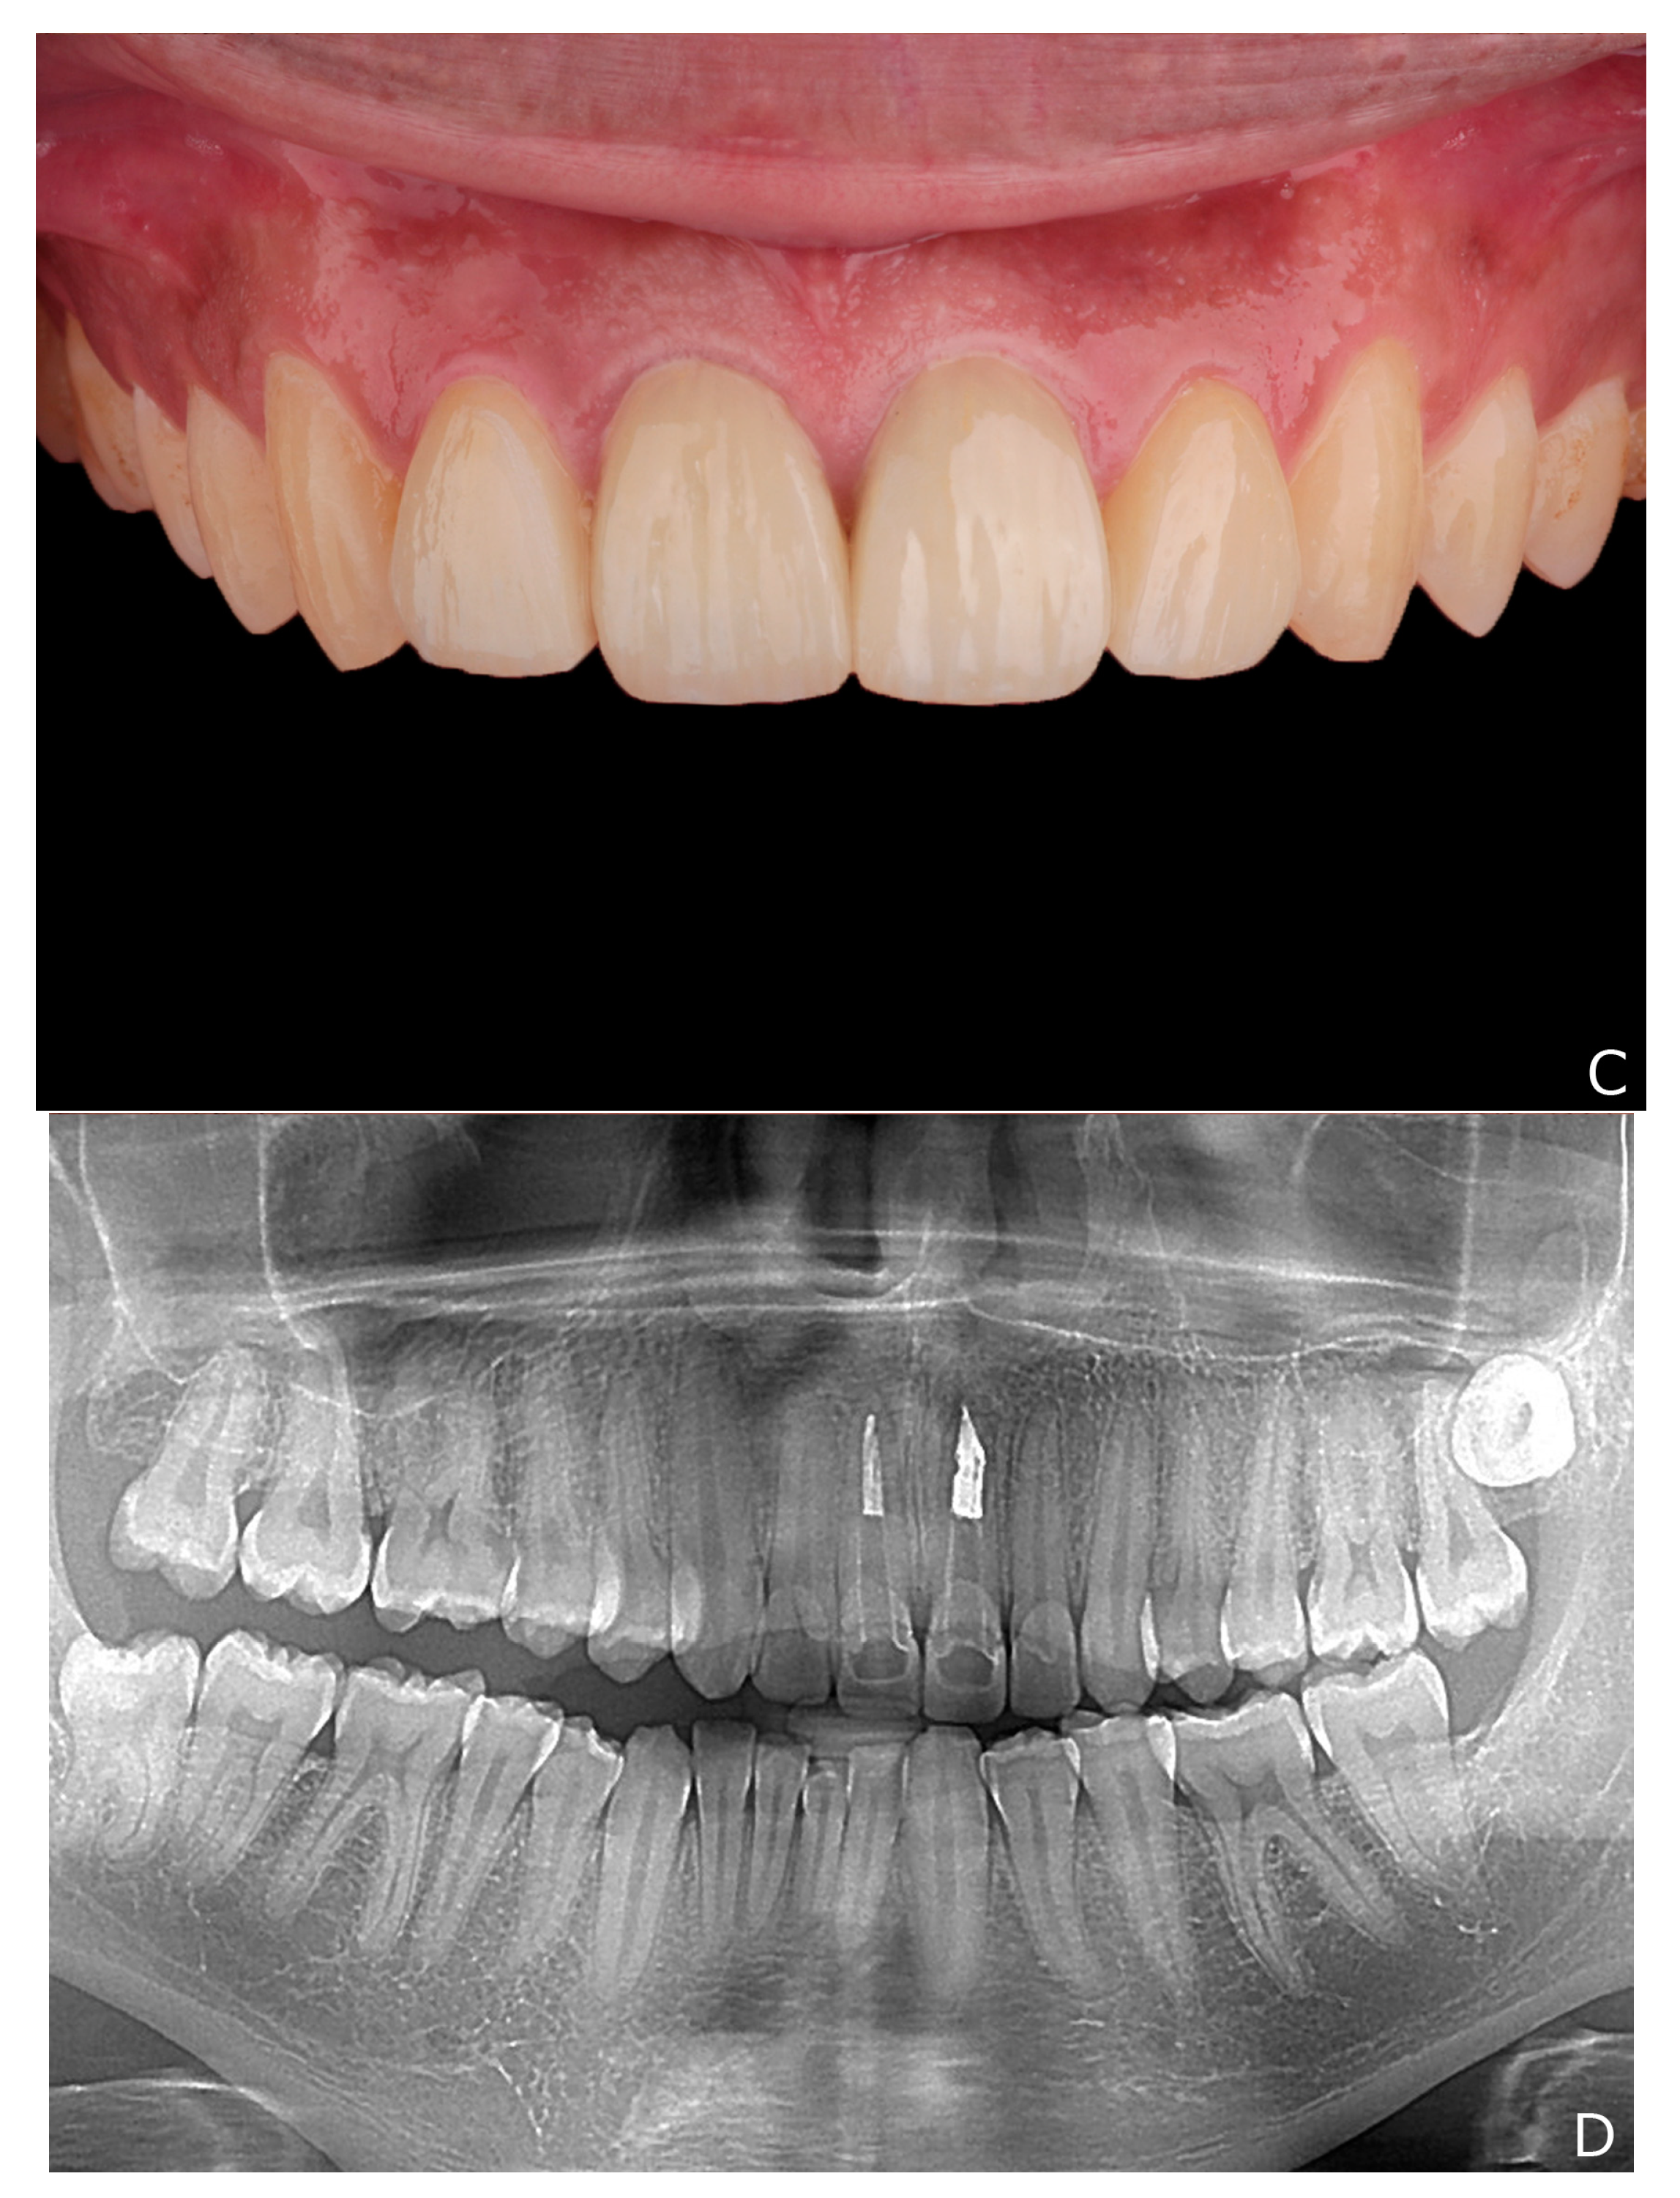

2. Clinical Report